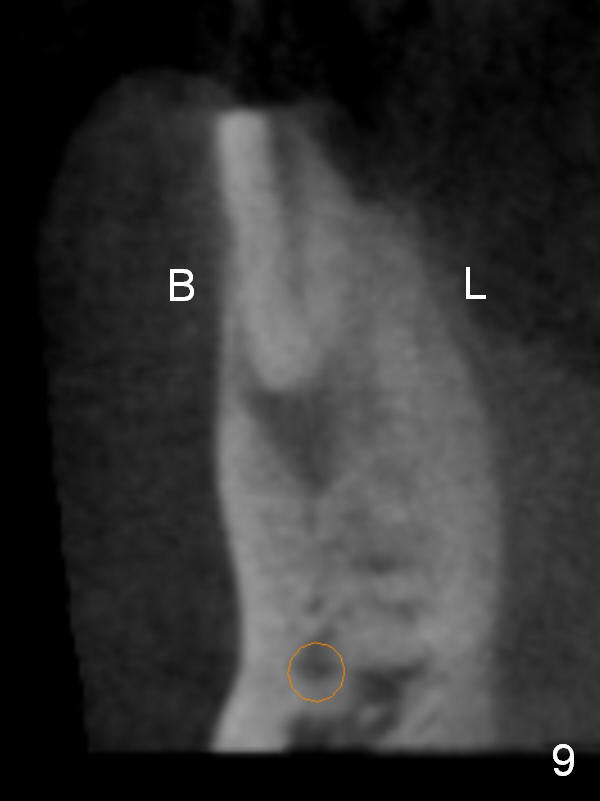

CT sagittal section shows that it is possible to place 4.5x20 mm implant (Fig.6). Axial (Fig.7) and coronal (Fig.9) sections show that the lingual (L) plate is much thicker than the buccal (B) one. To prevent the implant being buccally deviated, a Lindermann bur is used after extraction (black area in Fig.8,10) to remove ~ 1mm bone from the lingual plate (red area in Fig.8,11). A 2 mm pilot drill is placed as lingual as possible (green in Fig.8,11). If the implant (Fig.12) starts to deviate buccally while being placed, remove it from the osteotomy and remove more bone from the lingual plate. Place the implant again and monitor the trajectory tightly.